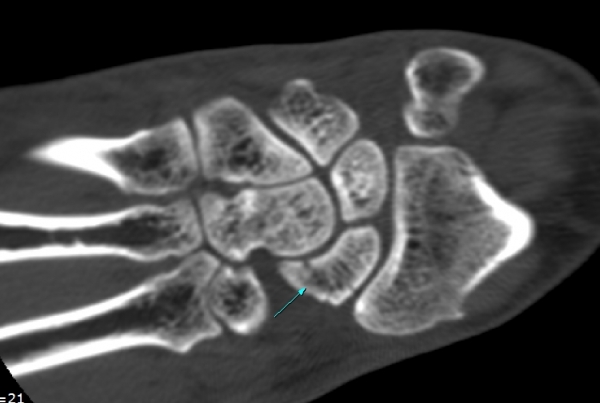

CT °Ë»ç

È®ÁøÀ» À§ÇÑ ÃÊÀ½ÆÄ°Ë»ç¿¡¼ ÁÖ»ó°ñ °ñÀý È®ÀÓ µÊ.

ÁÖÁöÇÏ´Ù½ÃÇÇ ÁÖ»ó°ñ °ñÀýÀº ´Ü¼ø¹æ»ç¼±°Ë»ç¿¡¼ È®ÀεÇÁö ¾Ê´Â °æ¿ì°¡ ÈçÇѵ¥